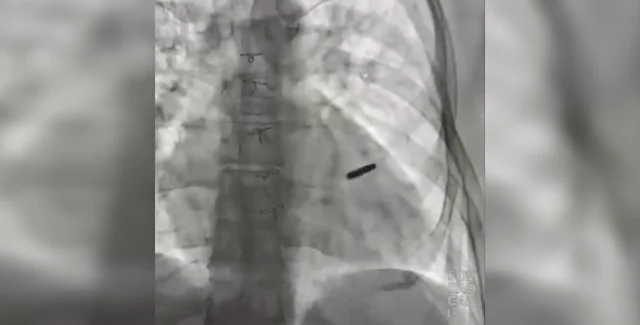

Захисника Маріуполя захопили у полон пораненим, але за три роки росіяни не провели йому операцію, щоб дістати з серця кулю. Український лікар Борис Тодуров наголосив, що українцю пощастило вижити, а тепер загроза в минулому.

"Знаходилась у серці нашого хлопця, який три роки провів у полоні. Захищав разом з азовцями "Азовсталь". Пораненого взяли в полон під час атаки на Маріуполь", — заявив директор Інституту серця МОЗ України Борис Тодуров, демонструючи кулю просто в операційній.

"І три роки він був з цією кулею, прожив. На щастя, вони нічого не пошкодила. Зараз ми її видалили. Пощастило хлопцю. Думаю, що проживе довге і щасливе життя", — підкреслив лікар.

Медики також показали, як до операції билося серце пацієнта з кулею всередині. Ім'я захисника "Азовсталі", який прожив три роки з кулею у серці, наразі невідоме.